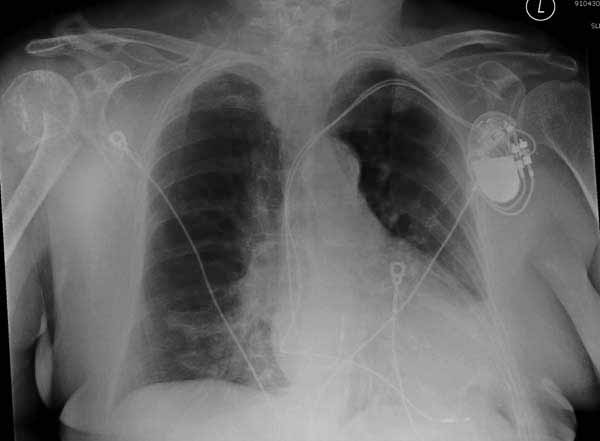

Уважаемы коллеги! Прошу помочь определиться с тактикой лечения пациентки. В феврале в отделение поступила пациентка с оскольчатым переломо-вывихом головки плечевой кости. Выполнена операция -остеосинтез блокируемой пластиной. Костная пластика не производилась. На контрольных рентгенограммах остается сублюксация головки и смещение большого бугорка. Интраоперационно бугорок подшивался с помощью лавсановых нитей. Послеоперационно: ношение косыночной повязки и пассивные движения в плечевом суставе в течение 2,5-х месяцев без особенностей. Через 2,5 месяца при попытке выполнения пассивно-активных движений произошел передний вывих плечевой кости.Вся реабилитация производилась по месту жительства. Таким образом существование вывиха в течение 1 месяца. Боли не беспокоят. Нейрососудистых нарушений в конечности нет. Что вы можете посоветовать: пластику, эндопротез, артродез? Заранее спасибо.

мне кажется ,что на послеоперационном снимке, также имеется сублюксация головки.сколько годов пациентке?

Уважаемый коллега. На мой взгляд имеющаяся дислокация головки обусловлена на мой взгляд имеющейся у пациента обширной травмой ротаторного аппарата. В пользу данной точки зрения могу привести следующее: на представленных Вами рентгенограммах хорошо заметен отрыв большого бугорка со смещением отломков который как известно является точкой прикрепления коротких наружных ротаторов плеча. Последующая миграция данного фрагмента и неполноценная репозиция его при первичном остеосинтезе с нестабильной фиксацией на мой взгляд и обусловили создавшуюся ситуацию. то что пациента не беспокоят боли позволю подвергнуть сомнению поскольку сам занимаюсь хирургией плеча и с подобными ситуациями сталкивался неоднократно. На мой взгляд в настоящее время целесообразно проведение повторного оперативного вмешательства с адекватным восстановлением ротаторного аппарата, поскольку дальнейшее затягивание сложившейся ситуации уменьшает шанс на успех данного вмешательства.

Набор мелких снимков не отражает истинную картину суставной поверхности лопатки, а также качество репозиции головки плеча. Необходимо доказать аксиальным снимком наличие покрытия головки. Правильная маркировка на рентген снимках и соответствие с выставленным диагнозом гарантирует от ошибок со стороной во время операции!

Здесь результат похожего случая, больная 87 лет, отягощенная сердечными делами и два года назад установка pacemaker и нескольких стентов. На третий день, сегодня утром сделали операцию. Послеоперационный псевдовывих связанный с релаксацией мышц и общим обезболиванием.

Для адекватного лечения необходимо знать состояние костного компонента - нужно КТ с артрографией что поможет частично оценить состояние сухожилий и лабриум. Уже по снимку можно сказать что существует большой костный дефект в задне-наружном сегменте.